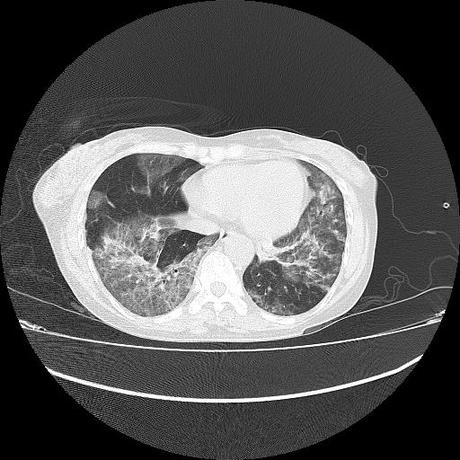

El parénquima pulmonar con areas parcheadas difusas en vidrio despulido combinadas con otras areas hipodensas de baja atenuación debidas a atrapamiento aéreo y engrosamiento intersticial y zonas de fibrosis de predominio en lóbulos medios e inferiores de ambos pulmones.

- LOS HALLAZGOS PUEDEN ESTAR EN RELACIÓN A NEUMOPATIA INTERSTICIAL PROBABLE ETIOLOGIA HIPERSENSITIVA VS AUTOINMUNE/BACTERIANA/FUNGICA.